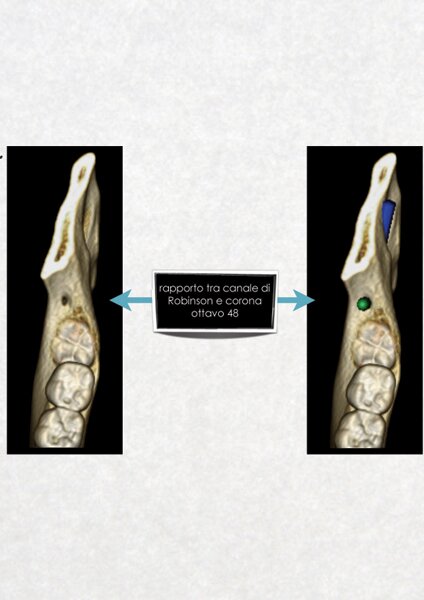

La diagnostica dei casi complessi di chirurgia orale ed implantologia è realizzata, a partire da una TAC dentale a cui si sottopone il paziente, mediante l'utilizzo del software computerizzato ONE SCAN 3D. Attraverso questo programma è possibile ottenere una ricostruzione tridimensionale del mascellare/mandibola del paziente, identificare le strutture anatomiche di riferimento, valutare i tessuti duri e molli, pianificare l'inserimento degli impianti nell'osso disponibile e ottenere un valido consenso informato del paziente all'intervento chirurgico.

Questo approccio moderno e tecnologico consente all'odontoiatra di lavorare con la massima serenità,riducendo al minimo qualsiasi imprevisto in fase operatoria.